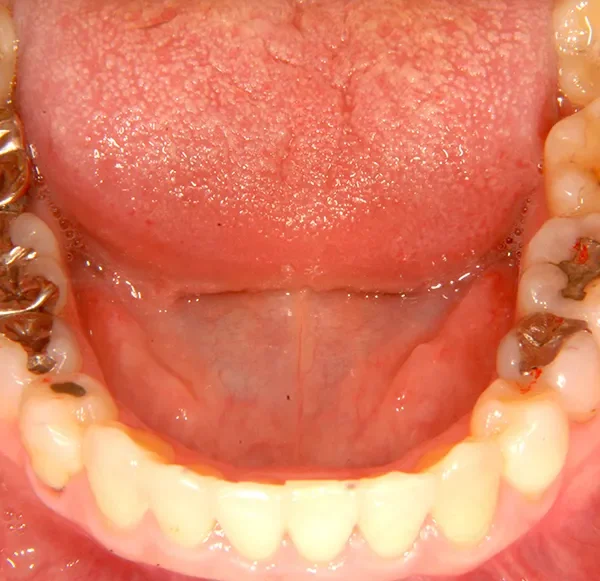

初診時年齢 40歳以上 (女性) 主訴 上下のがたがた・噛み合わない

診断名 叢生 装置名

状態 ガタガタ・でこぼこに生えている(叢生)

八重歯(叢生)

上下のがたがたと噛み合わない事を主訴に来院されました。

歯は抜かずに矯正治療しました。

治療回数35回、2年8ヶ月の治療期間で矯正治療を終了しました。